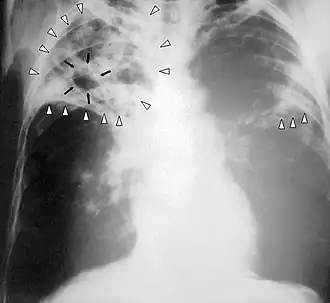

Röntgenfoto

In de tuberculosebestrijding wordt voor het aantonen van tuberculose in en bij de longen veel gebruikgemaakt van longfoto's. Longtuberculose geeft nagenoeg altijd een zichtbare fotoafwijking. Bij een slechte immuunstatus, bijvoorbeeld door hiv en aids, wordt de foto net als de mantouxtest minder betrouwbaar, omdat de afwijkingen kunnen afnemen.